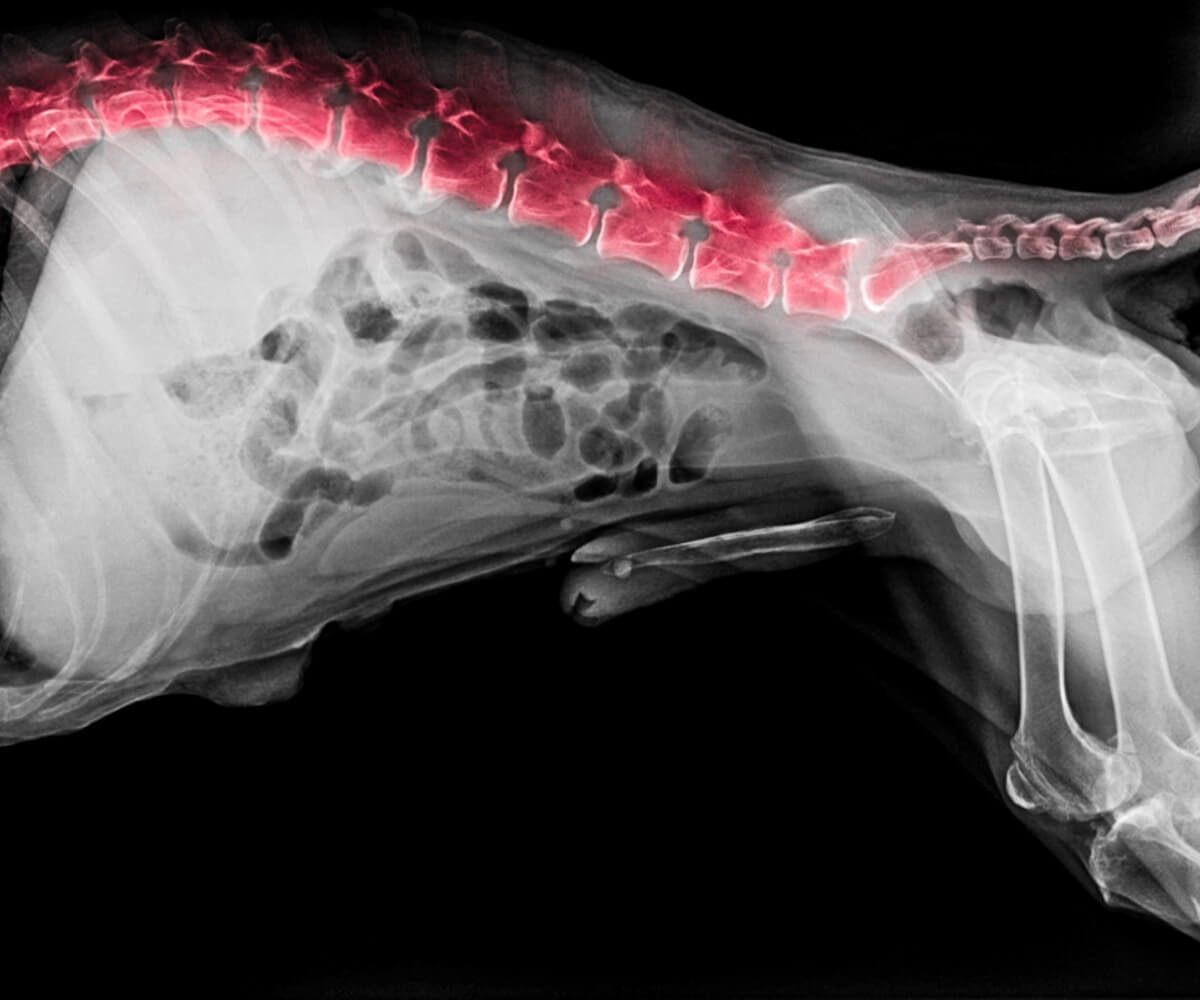

Les méthodes de diagnostic

Comme vous l’avez peut-être remarqué, les problèmes de dos chez les chiens sont très similaires les uns aux autres. Par conséquent, l’utilisation d’outils de diagnostic sera d’une grande aide pour définir le processus que traverse l’animal. Les méthodes diagnostiques principales et les plus efficaces actuellement utilisées en clinique sont les suivantes :

- Plaques radiographiques (avec ou sans contraste).

- Tomodensitométrie.

- Résonance magnétique.

- Prélèvement (liquide céphalo-rachidien).